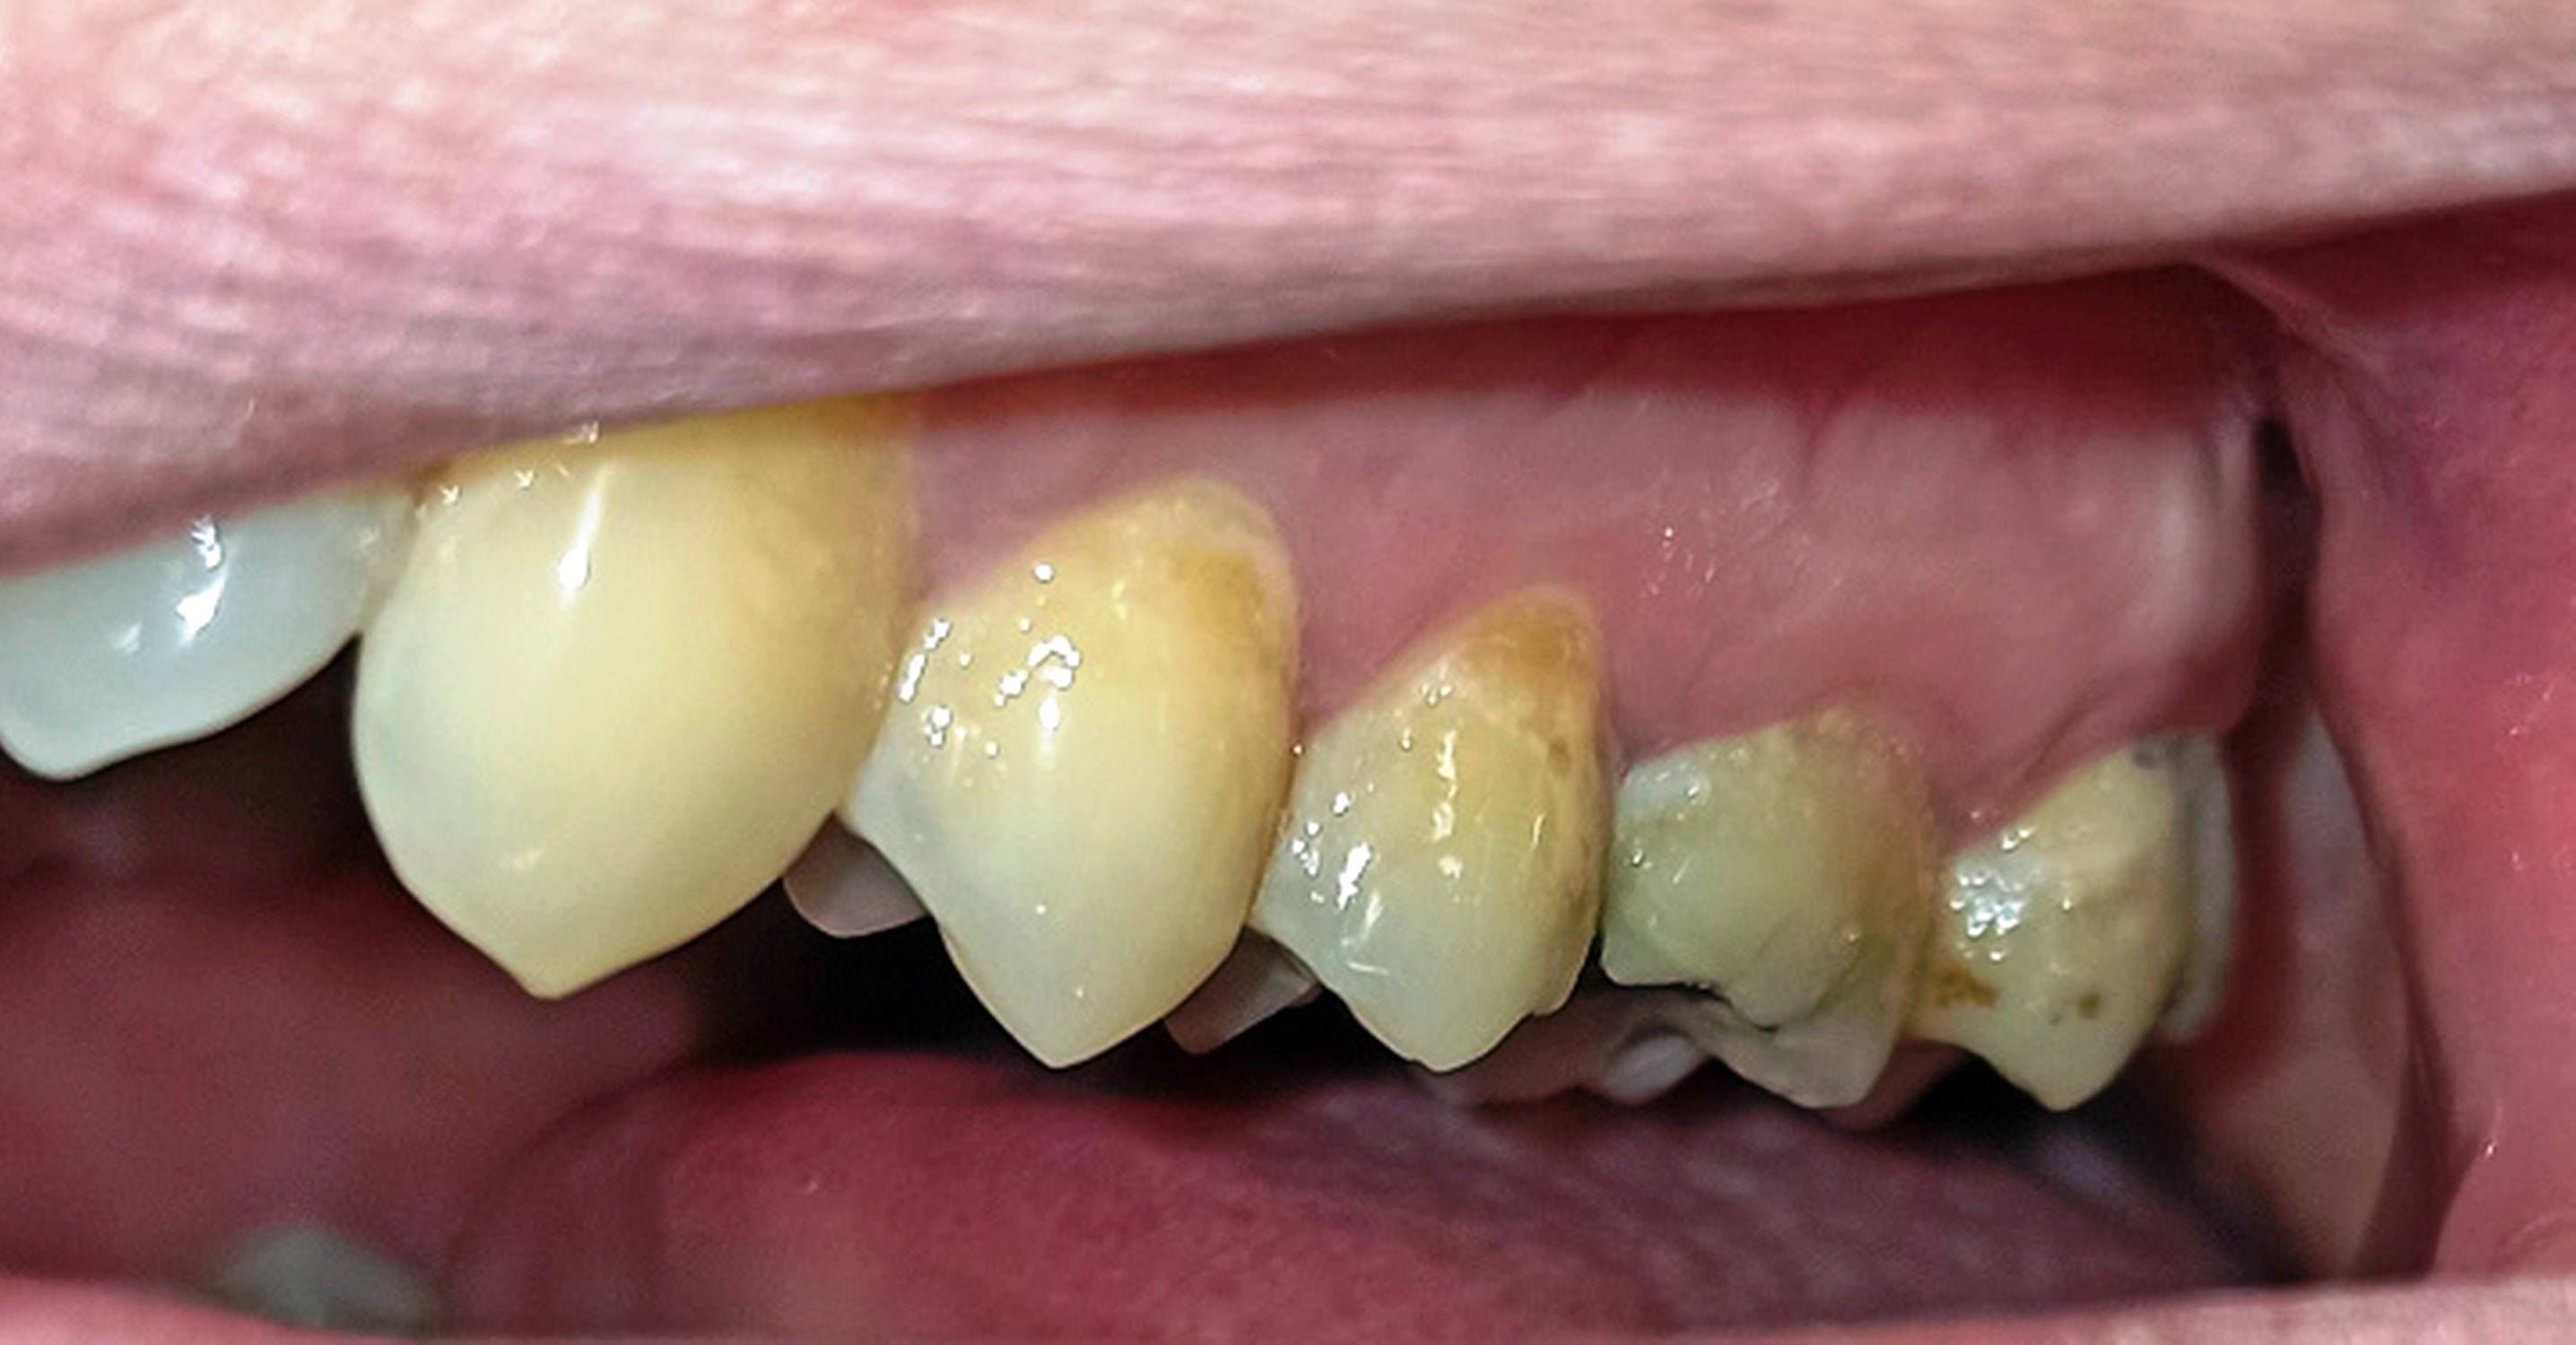

Innerhalb der Gruppe der Patienten mit Fazialisparese wurde außerdem ein Vergleich der Mundgesundheit zwischen beiden Mundhälften durchgeführt. Dabei wies die paretische Seite eine signifikant höhere Plaque-Kontamination, mehr Blutungen und höhere PSI-Werte auf als die nicht paretische Seite (Tab. 3). Die Plaque-Kontamination war in Bezug auf den API auf der paretischen Seite um 10,9 % (p = 0,004) höher als auf der nicht paretischen Seite. Ebenso wiesen die vestibulären Zahnoberflächen der paretischen Seite mehr Biofilm auf als die der nicht paretischen Seite (p = 0,002; s. Tab. 3, Abb. 2a und b). Dabei war der Unterschied bei den männlichen Patienten (0,8 vs. 0,5; p = 0,001) größer als bei den weiblichen Patienten (0,6 vs. 0,4; p = 0,002). Außerdem wurde bei Patienten mit rechtsseitiger Fazialisparese ein größerer Seitenunterschied (0,7 vs. 0,5; p < 0,001) dokumentiert als bei Patienten mit linksseitiger Fazialisparese (0,5 vs. 0,4; p = 0,043). Ursächlich erschien die Händigkeit der Patienten. Während bei Patienten mit linksseitiger Fazialisparese die Erkrankung auf der für Rechtshänder besser zu reinigenden Mundhälfte vorlag, waren rechtshändige Patienten mit rechtsseitiger Fazialisparese einer doppelten Belastung ausgesetzt (18). Die Gingivablutung nach Sondierung war auf der paretischen Seite ebenfalls signifikant höher als auf der nicht paretischen Seite (s. Tab. 3). Das spiegelte sich sowohl bei den Werten des SBI (s. Tab. 3, Abb. 3) als auch bei den Werten des PBI (s. Tab. 3, Abb. 4a und b) wider. Die Sondierungstiefen waren auf der paretischen Seite im Vergleich zur nicht paretischen Seite tiefer und der Attachmentverlust war höher. Dabei konnte jedoch kein signifikanter Unterschied nachgewiesen werden. Der mittlere PSI erreichte auf der paretischen Seite signifikant höhere Werte als auf der nicht paretischen Seite (p = 0,032; s. Tab. 3), was auf eine schlechtere Gingivagesundheit hinweist. Darüber hinaus war die Prävalenz unbehandelter kariöser Läsionen auf der paretischen Seite höher als auf der nicht paretischen Seite (s. Tab. 3). Ein Fallbeispiel illustriert eindrucksvoll die Unterschiede zwischen der kariesfreien nicht paretischen Seite und der paretischen Seite mit multiplen aktiv kariösen Läsionen (Abb. 5a und b). Zusätzlich wies die paretische Seite eine höhere Anzahl an Restaurationen auf als die nicht paretische Seite (s. Tab. 3). Hinsichtlich des Zahnsteinbefalls wurden auch im Seitenvergleich der Mundhälften keine signifikanten Unterschiede zwischen den paretischen und den nicht paretischen Seiten festgestellt. Im Einzelfall wurden jedoch eindrucksvolle Unterschiede zwischen den Mundhälften deutlich (Abb. 6a und b).